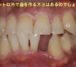

右下2本歯が無い患者さん、、、インプラントで歯を作ってほしいとのこと

インプラントを2本埋入していきました

今回、2本ともISQ70以上でしたので、そのまま仮歯をつくっていきます

いかがでしょうか?

その日のうちに歯が入り、患者さんにとても喜んでいただきました